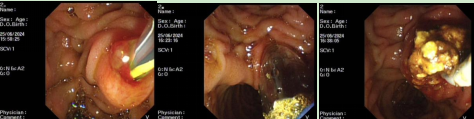

病例3

患者,女,76岁,主因“间断上腹部饱胀不适伴疼痛1个月”就诊我科,既往胆囊切除史。腹部CT提示胆总管结石。因患者结石较大,行内镜下逆行胰胆管造影术并给予胆道支架置入治疗。术后患者病情平稳,恢复良好。择期行内镜下胆总管结石取石治疗。